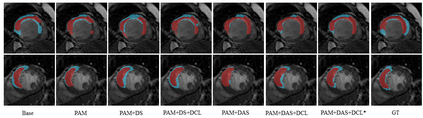

Multi-sequence cardiac magnetic resonance (CMR) provides essential pathology information (scar and edema) to diagnose myocardial infarction. However, automatic pathology segmentation can be challenging due to the difficulty of effectively exploring the underlying information from the multi-sequence CMR data. This paper aims to tackle the scar and edema segmentation from multi-sequence CMR with a novel auto-weighted supervision framework, where the interactions among different supervised layers are explored under a task-specific objective using reinforcement learning. Furthermore, we design a coarse-to-fine framework to boost the small myocardial pathology region segmentation with shape prior knowledge. The coarse segmentation model identifies the left ventricle myocardial structure as a shape prior, while the fine segmentation model integrates a pixel-wise attention strategy with an auto-weighted supervision model to learn and extract salient pathological structures from the multi-sequence CMR data. Extensive experimental results on a publicly available dataset from Myocardial pathology segmentation combining multi-sequence CMR (MyoPS 2020) demonstrate our method can achieve promising performance compared with other state-of-the-art methods. Our method is promising in advancing the myocardial pathology assessment on multi-sequence CMR data. To motivate the community, we have made our code publicly available via https://github.com/soleilssss/AWSnet/tree/master.